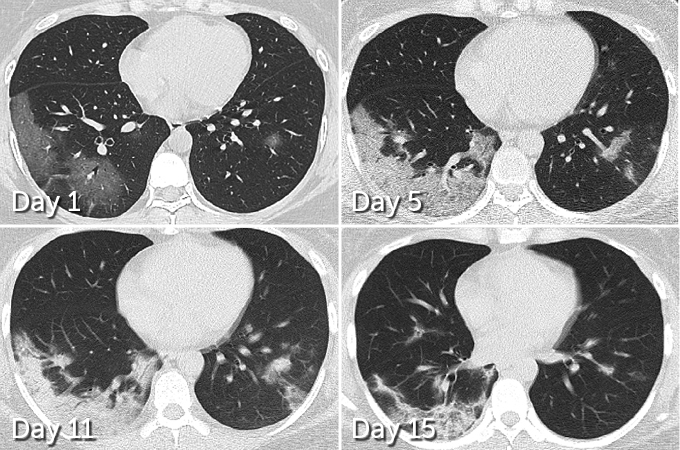

Patchy spots often show up in lung scans of actively sick COVID-19 patients (colorized scan shown). Some lung damage could be long-lasting, new research suggests.

In 70 patients who survived COVID-19 pneumonia, 66 had some level of lung damage visible in CT scans taken before hospital discharge, researchers report March 19 in Radiology. The damage ranged from dense clumps of hardened tissue blocking blood vessels within the tiny air sacs called alveoli, which absorb oxygen, to tissue lesions around the alveoli, Yuhui Wang, a radiologist at Huazhong University of Science and Technology in Wuhan, China, and colleagues found.

But while initial lung images indicate that SARS and MERS typically set into just one lung, COVID-19 appears to be more likely to afflict both lungs right away. In 75 of the 90 patients admitted to Huazhong University Hospital with COVID-19 pneumonia from January 16 to February 17, damage was seen across both lungs, Wang and colleagues report. CT scans taken before hospital discharge revealed that 42 out of 70 patients displayed the type of lesions around the alveoli that are more likely to develop into scars.